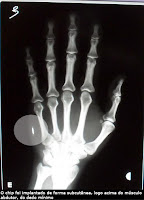

Imagem retirada do site do IFSC-USP

Vantagens e desvantagens à parte, sem dúvida é uma ideia muito interessante. Mário Gazziro, doutorando do Instituto de Física de São Carlos (IFSC/USP) e docente do Instituto de Ciências Matemáticas e da Computação (ICMC/USP), está desenvolvendo este projeto em que ele mesmo foi a "cobaia" ao implantar o chip na mão.